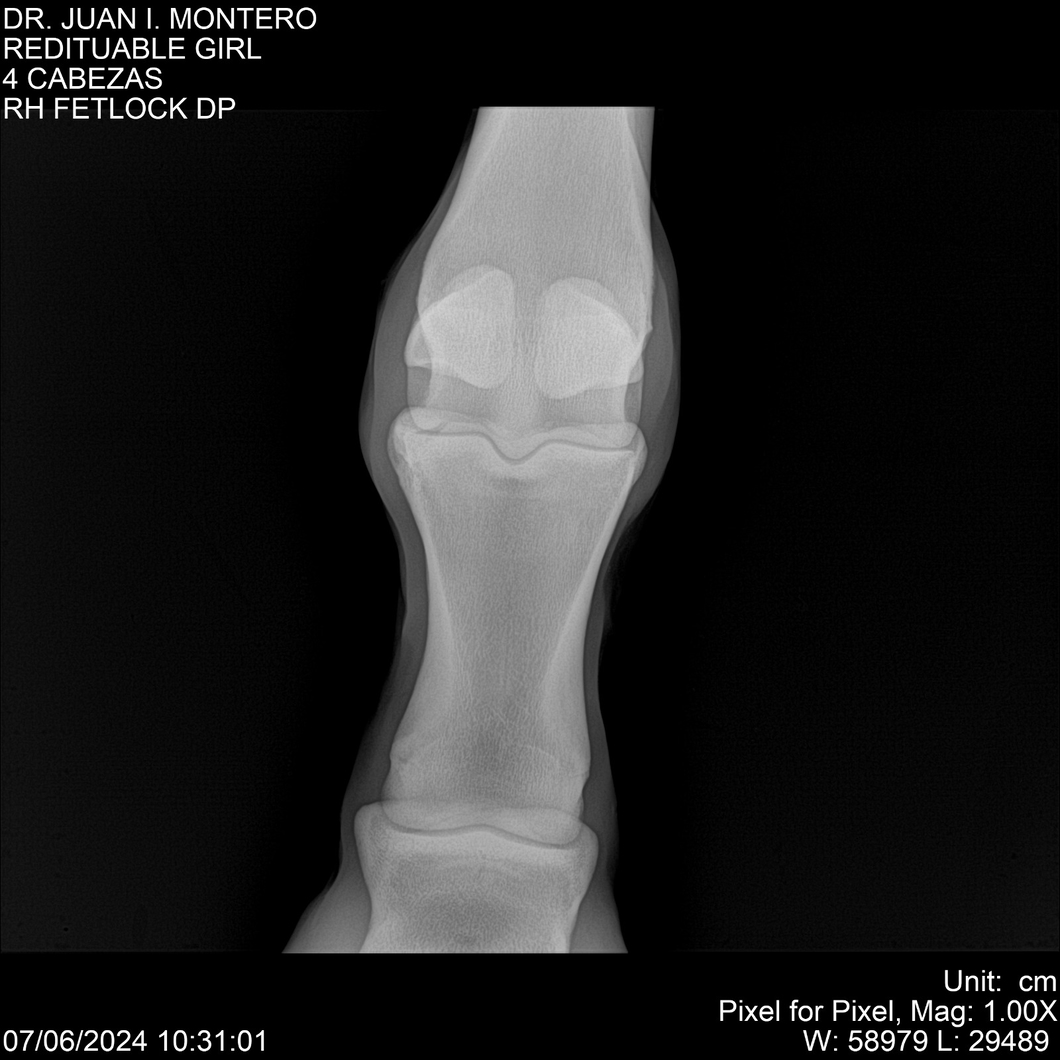

LOTE 19, REDITUABLE GIRL Lote Anterior Volver al remate Lote Siguiente Ficha Contacto Montevideo - Ficha del Lote Identificador: #281096 Categoría: Yeguarizos Montevideo - 79 Visualizaciones ClicData Contacto Empresa: Abelenda N. R., Walter Hugo Nombre*: Teléfono* : E-mail* : Mensaje Enviar Registrese gratis Este contenido Exclusivo está disponible sólo para usuarios registrados Ingresar